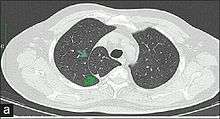

In human anatomy, an azygos lobe is a congenital variation of the upper lobe of the right lung.It is seen in 1% of the population. Embryologically, it arises from an anomalous lateral course of the azygos vein in a pleural septum within the apical segment of the right upper lobe or in other words an azygos lobe is formed when the right posterior cardinal vein, one of the precursors of the azygos vein, fails to migrate over the apex of the lung and penetrates it instead, carrying along two pleural layers that invaginates into the upper portion of the right upper lobe . As it has no bronchi, veins and arteries of its own or corresponding alteration in the segmental architecture of the lung, so it is not a true (misnomer), or even accessory, pulmonary lobe, but rather an anatomically separated part of the upper lobe. It is usually an incidental finding on chest x-ray or computed tomography and is as such not associated with any morbidity but can cause technical problems in thoracoscopic procedures .